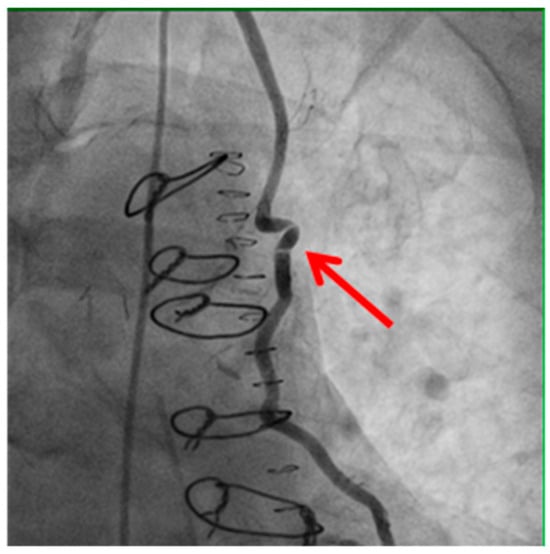

Technical issues remain a principal cause of PMI, with early graft thrombosis or occlusion being leading indications for uCAG (Figure 1, Figure 2, Figure 3 and Figure 4 illustrate typical technical causes, including proximal anastomotic stenosis, kinking, distal anastomotic stenosis, and misplaced anastomoses). Notable contributors include anastomotic stenosis, kinking, overstretching of grafts, and temporary graft spasm [,]. Prueßer et al. demonstrated that 30% of PMI cases detected via CAG were graft-related failures []. In this context, uCAG often reveals technical failures immediately post-surgery, providing the advantage of guiding targeted percutaneous coronary intervention or revascularization. Graft spasm, which can be relieved by nitrates, may also lead to acute ischemia. It refers to the temporary constriction of the bypass graft, reducing blood flow to the myocardium. This condition can be caused by various factors, including surgical trauma, inflammation, or the release of vasoactive substances [].

Figure 2.

Kinking of the bypass graft.

Example of bypass graft kinking (shown by the red arrow) detected on angiography. Kinking may compromise graft patency and myocardial perfusion, highlighting the importance of meticulous surgical technique and intraoperative assessment.